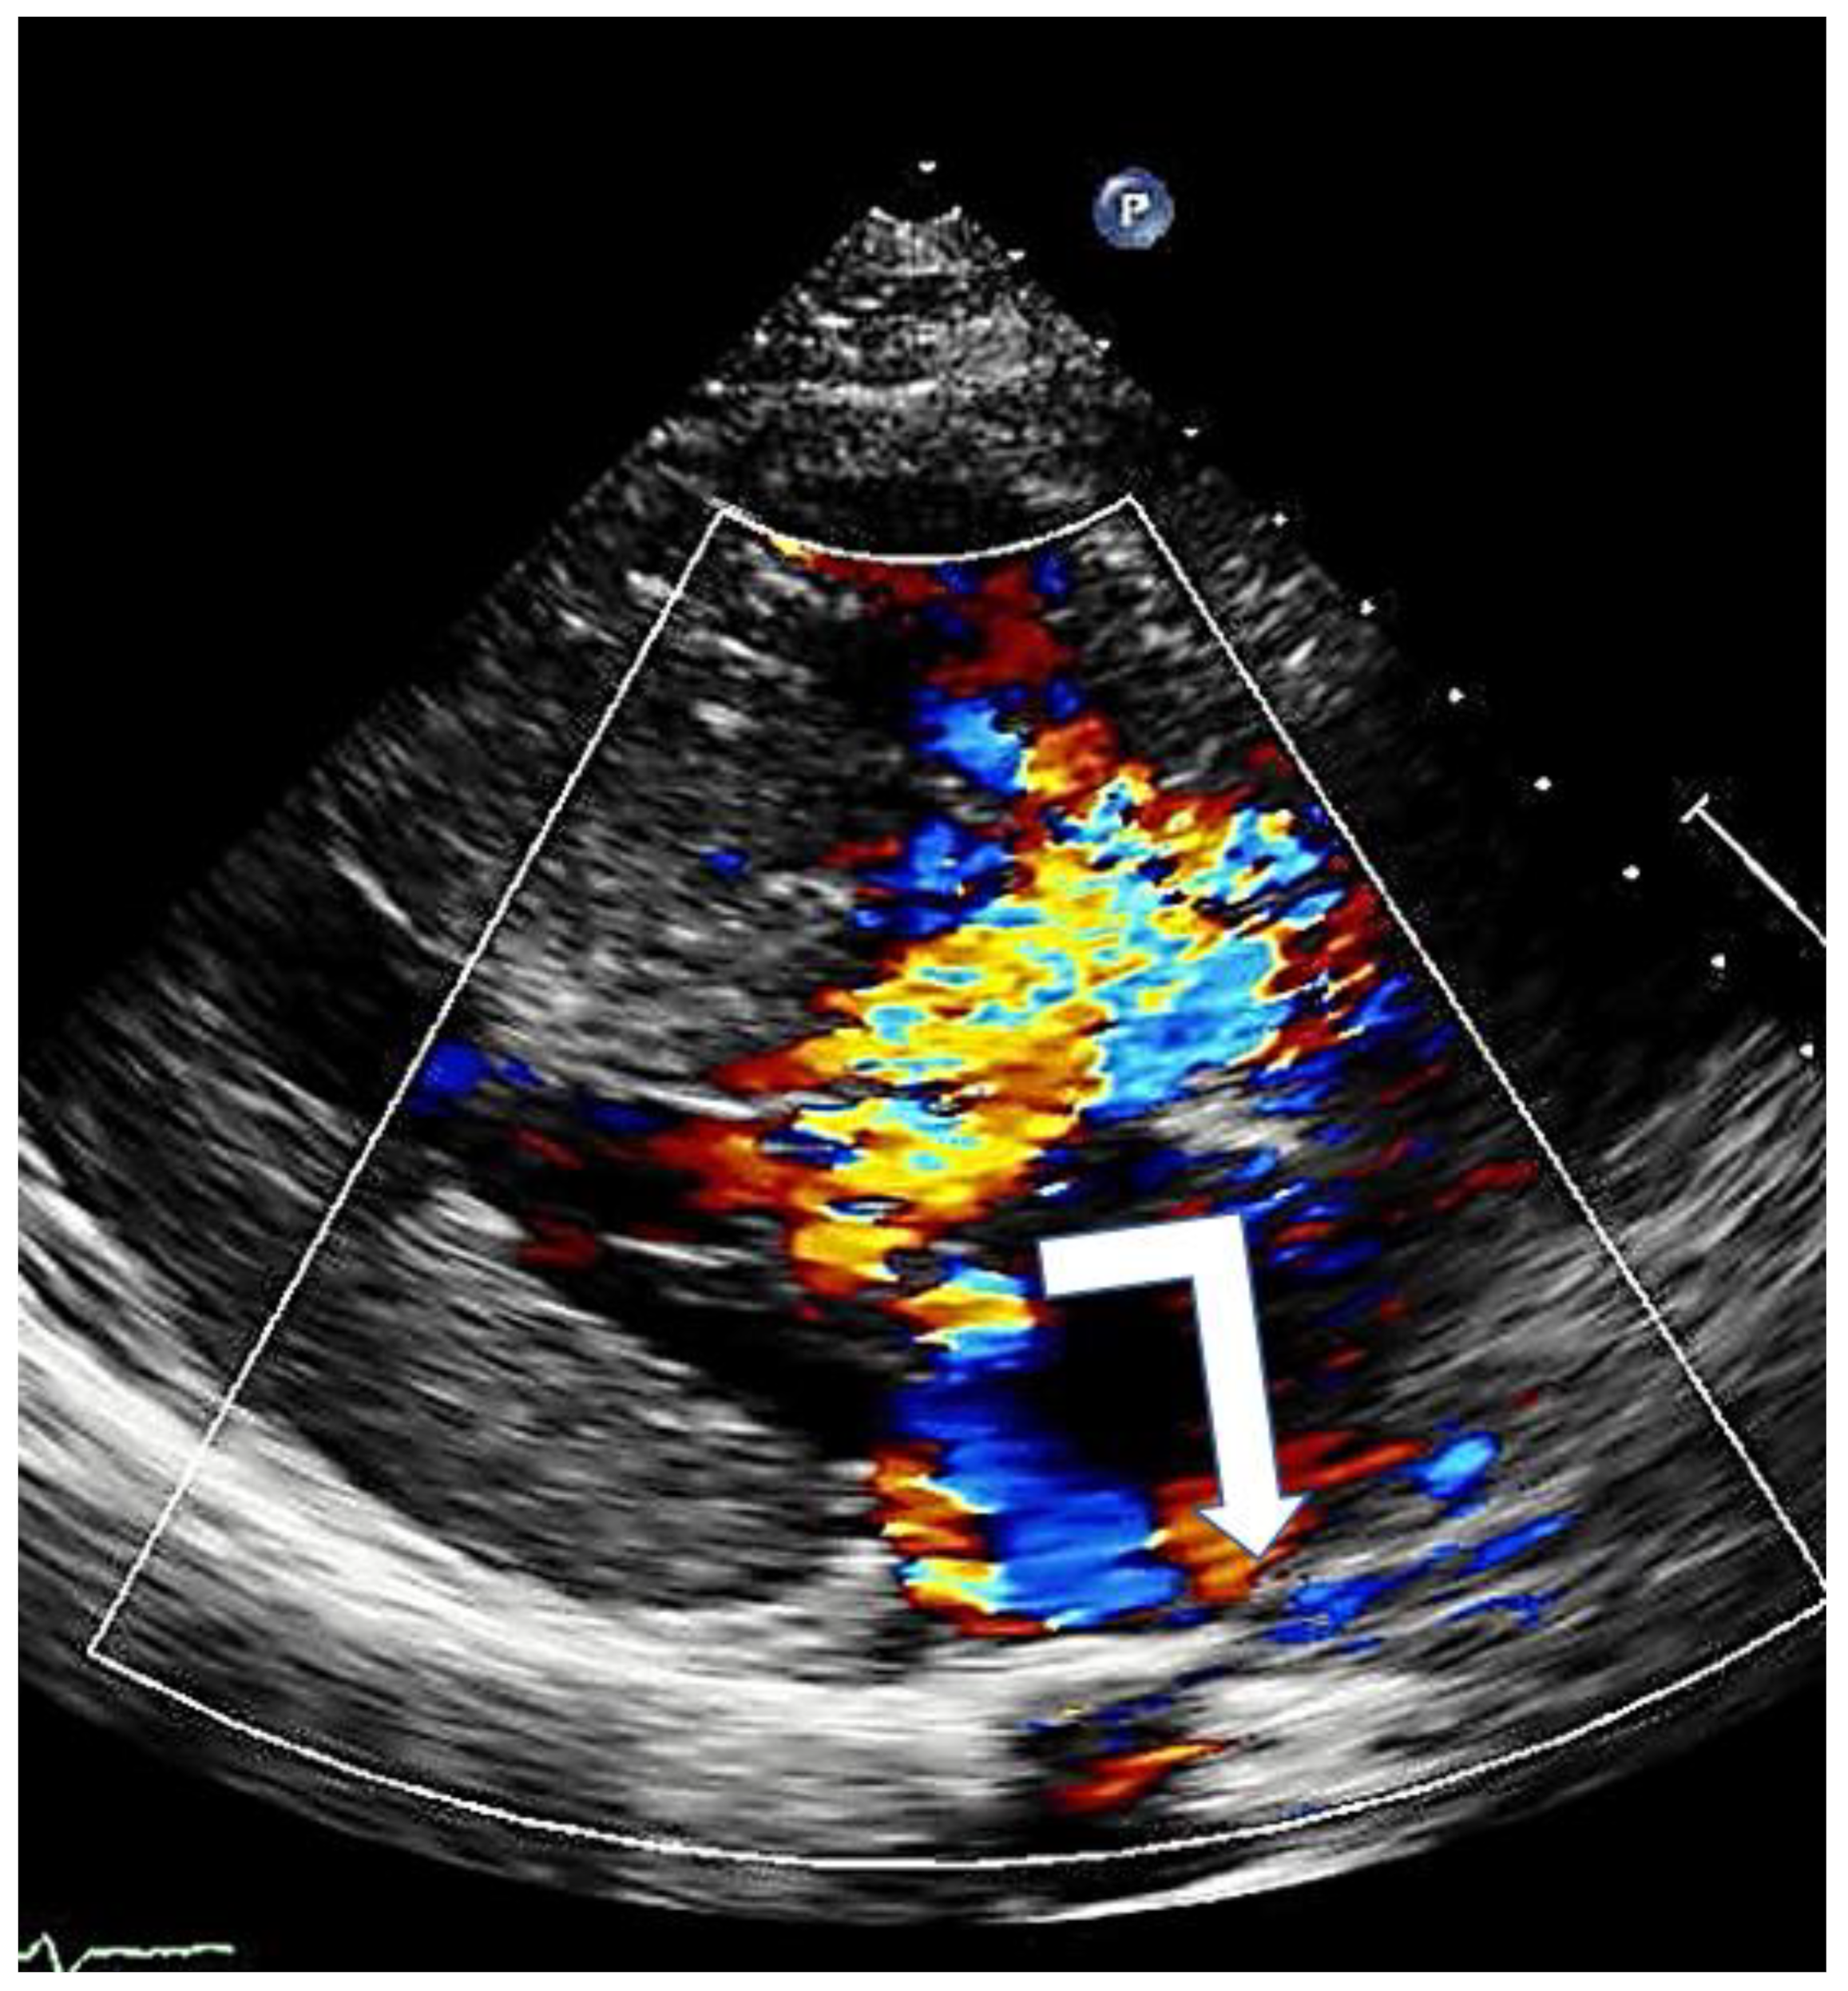

Color Doppler echocardiography identifies the presence and degree of mitral regurgitation and helps to understand the level at which obstruction occurs.

Mitral regurgitation (MR), caused by SAM, is observed in almost all patients with HOCM anterior mitral leaflet elongation and the associated increased mobility impairs adequate leaflet coaptation, resulting in SAM-related, eccentric posterior and lateral MR (Figure 6). When additional mitral valve abnormalities other than SAM are not observed, a direct relation between the pressure gradient and the severity of MR is evident. A central or anterior jet often indicates the presence of organic mitral valve disease [17].

Figure 6.

Mitral regurgitation in hypertrophic cardiomyopathy due to systolic anterior motion of the mitral valve; typical eccentric posterior direction (arrow).